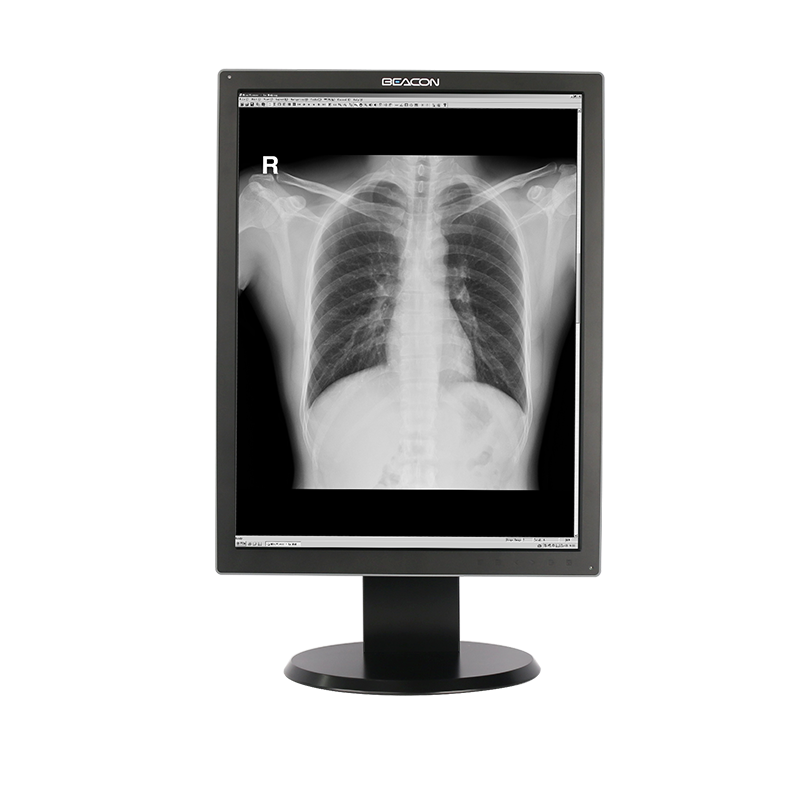

C510S tiene funciones de imagen en color y escala de grises, 5 millones de píxeles de resolución ultra alta, brillo ultra alto, contraste ultra alto, amplio ángulo de visión y bajo consumo de energía. Puede ser ampliamente utilizado en varios equipos de imágenes médicas incluyendo mama digital y sistema de PACS.

Las imágenes médicas, incluyendo los detalles más sutiles, se pueden visualizar con precisión. Mantener la coherencia de visualización entre diferentes pantallas, así como la visualización y las diferentes modalidades de imágenes, garantizar la precisión del diagnóstico.

Pantalla de diagnóstico

Pantalla de diagnóstico